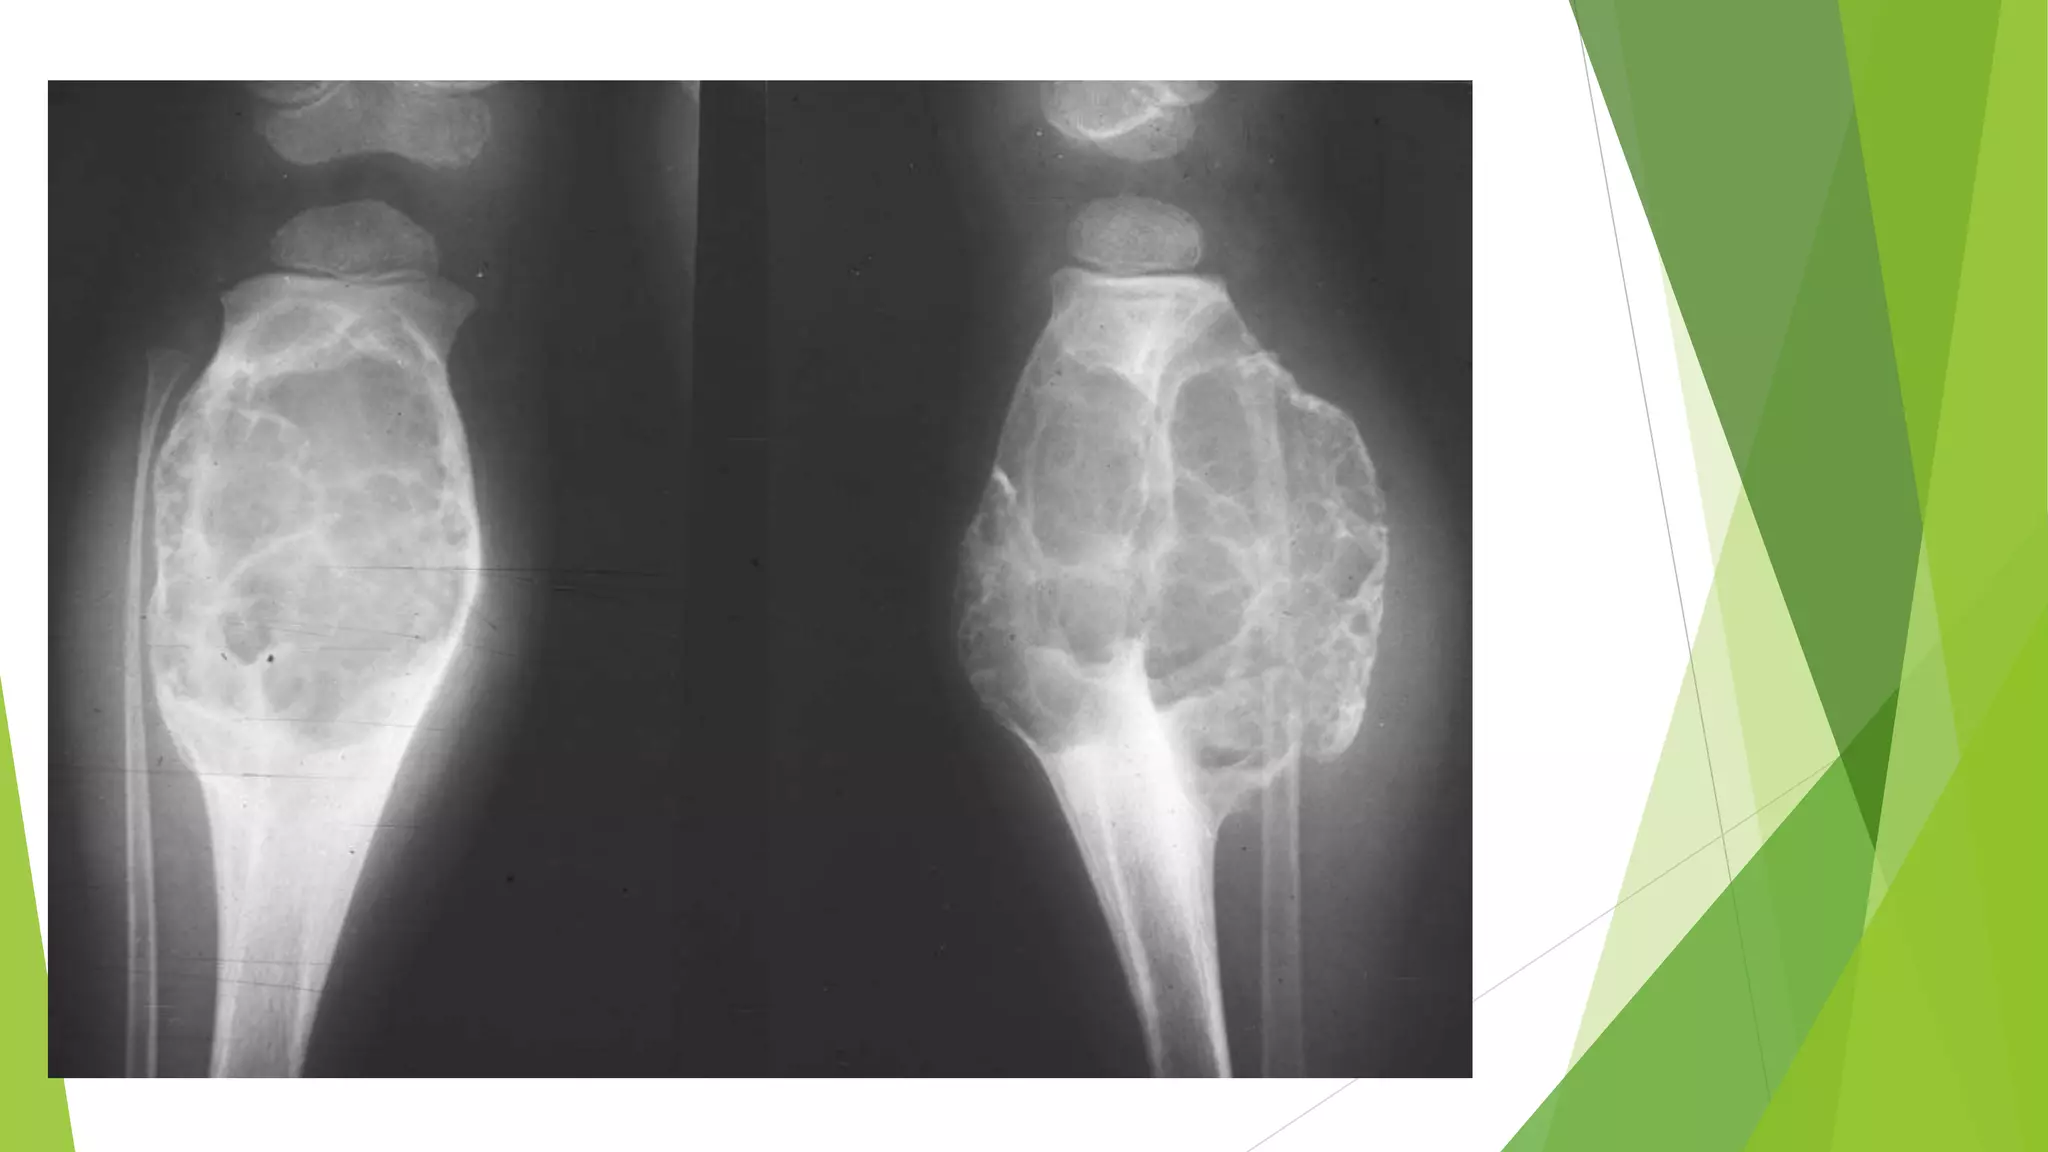

 Although almost any bone can be involved, the majority of

GCTs arise in the epiphysis of long bones around the knee

(distal femur and proximal tibia), frequently causing

arthritis-like symptoms.

 Radiographically, GCTs are large, purely lytic, and

eccentric

 The overlying cortex is frequently destroyed, producing a

bulging soft tissue mass with a thin shell of reactive bone.